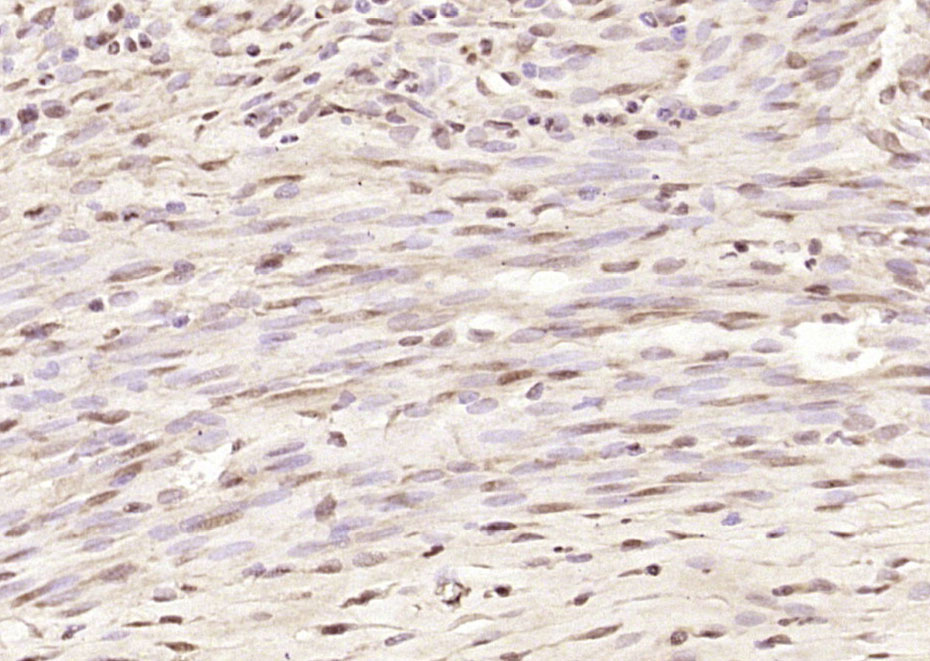

| 英文名称 | FANCA Rabbit pAb |

| 中文名称 | 范可尼贫血组蛋白A抗体 |

| 产品应用 | IHC-P=1:100-500, IHC-F=1:100-500, IF=1:100-500 Not yet tested in other applications. |

| 交叉反应 | Rat (Human, Mouse, Chicken, Rabbit) |

| {IHC-P} | {1:100-500} |

| {IHC-F} | {1:100-500} |

| {IF} | {1:100-500} |